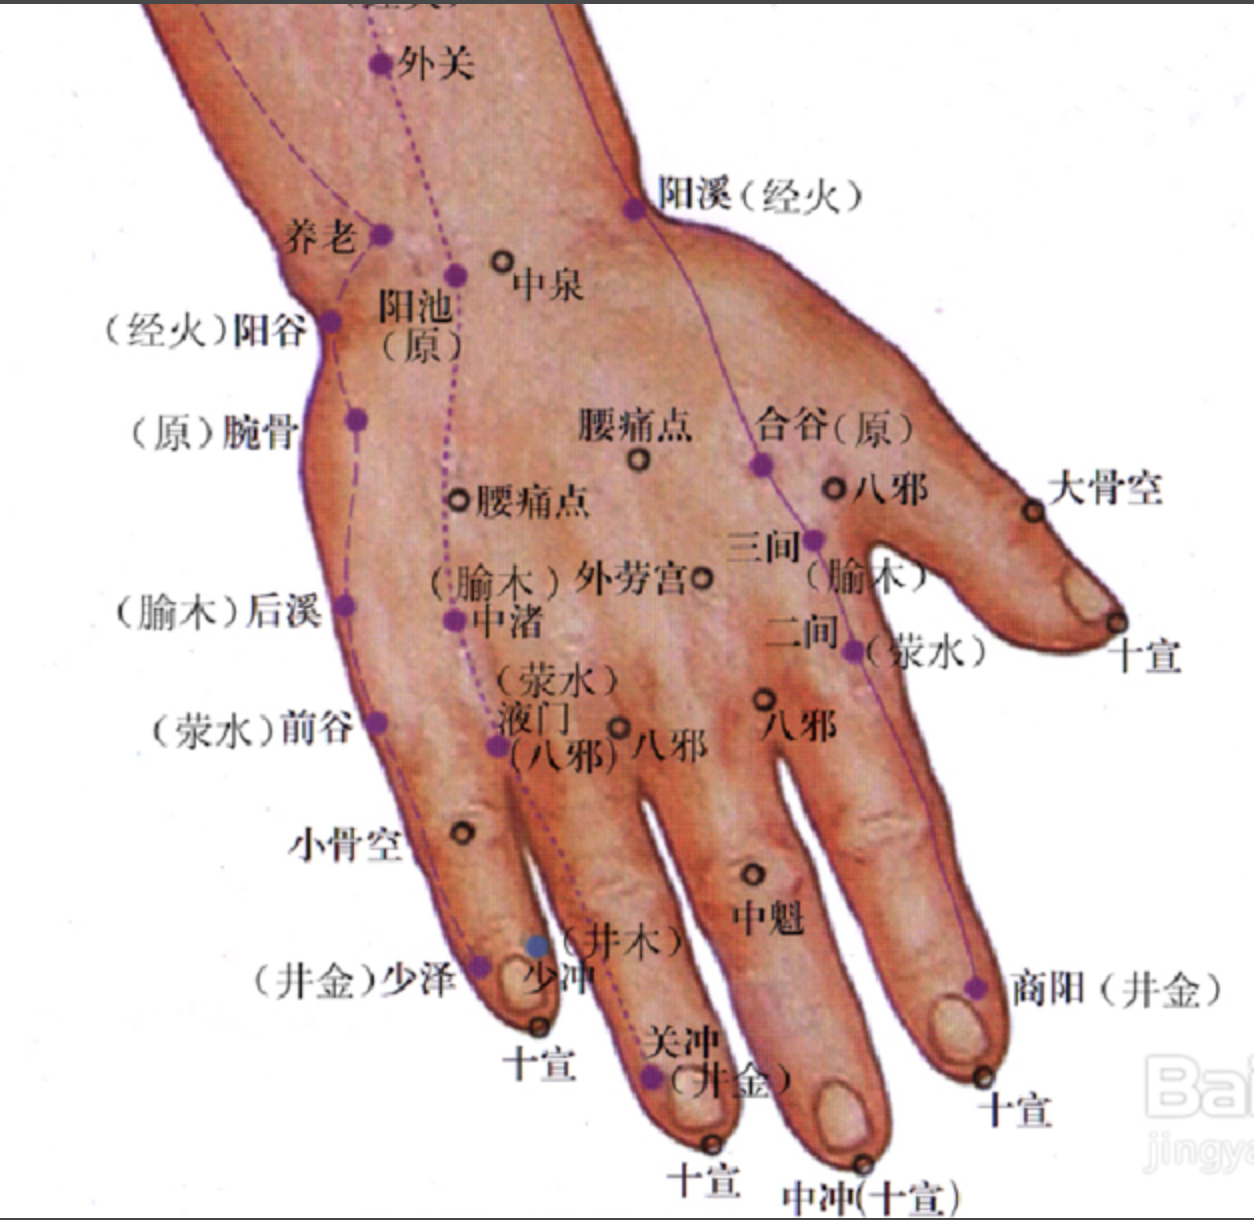

少泽

【定位】 在小指末节尺侧,距指甲角 0.1 寸(图 10-24-2)。

后溪

【定位】 在手掌尺侧,微握拳,当小指本节(第 5 指掌关节)后的远侧掌横纹头赤白肉际。